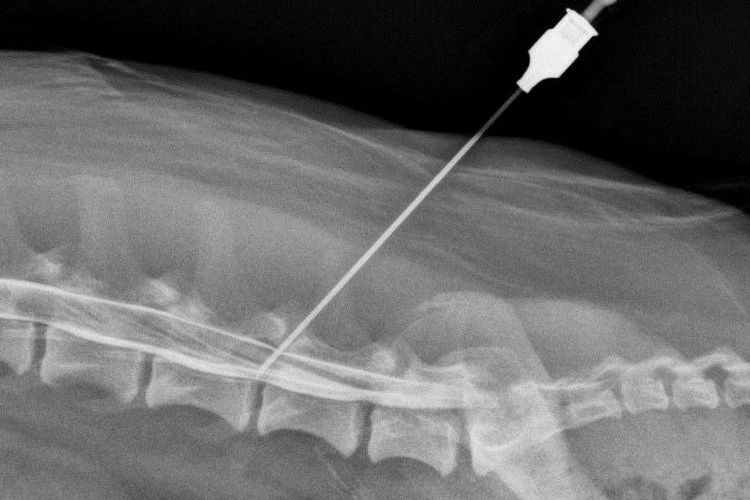

- Réaliser une radiographie.

Dans certains cas, une myélographie est prescrite : grâce à un agent de contraste, même les plus infimes modifications de la colonne vertébrale peuvent être visualisées.